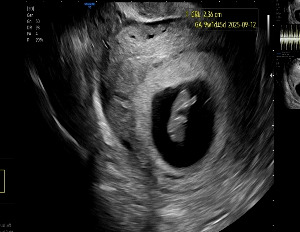

KakaoTalk_20250831_213642428_02.jpg 걱정과 달리 열심히 발차기 중인 찹쌀이

진료실에 들어가 초음파 검사를 먼저 진행했다.

찹쌀이는 여전히 건강하게, 분주히 움직이고 있었다.

초음파 진료가 끝나고 선생님이 NIPT 결과지를 보여주며 말했다.

“이상 없습니다. 전 항목 정상입니다.

그리고… 딸입니다. 축하드려요.”